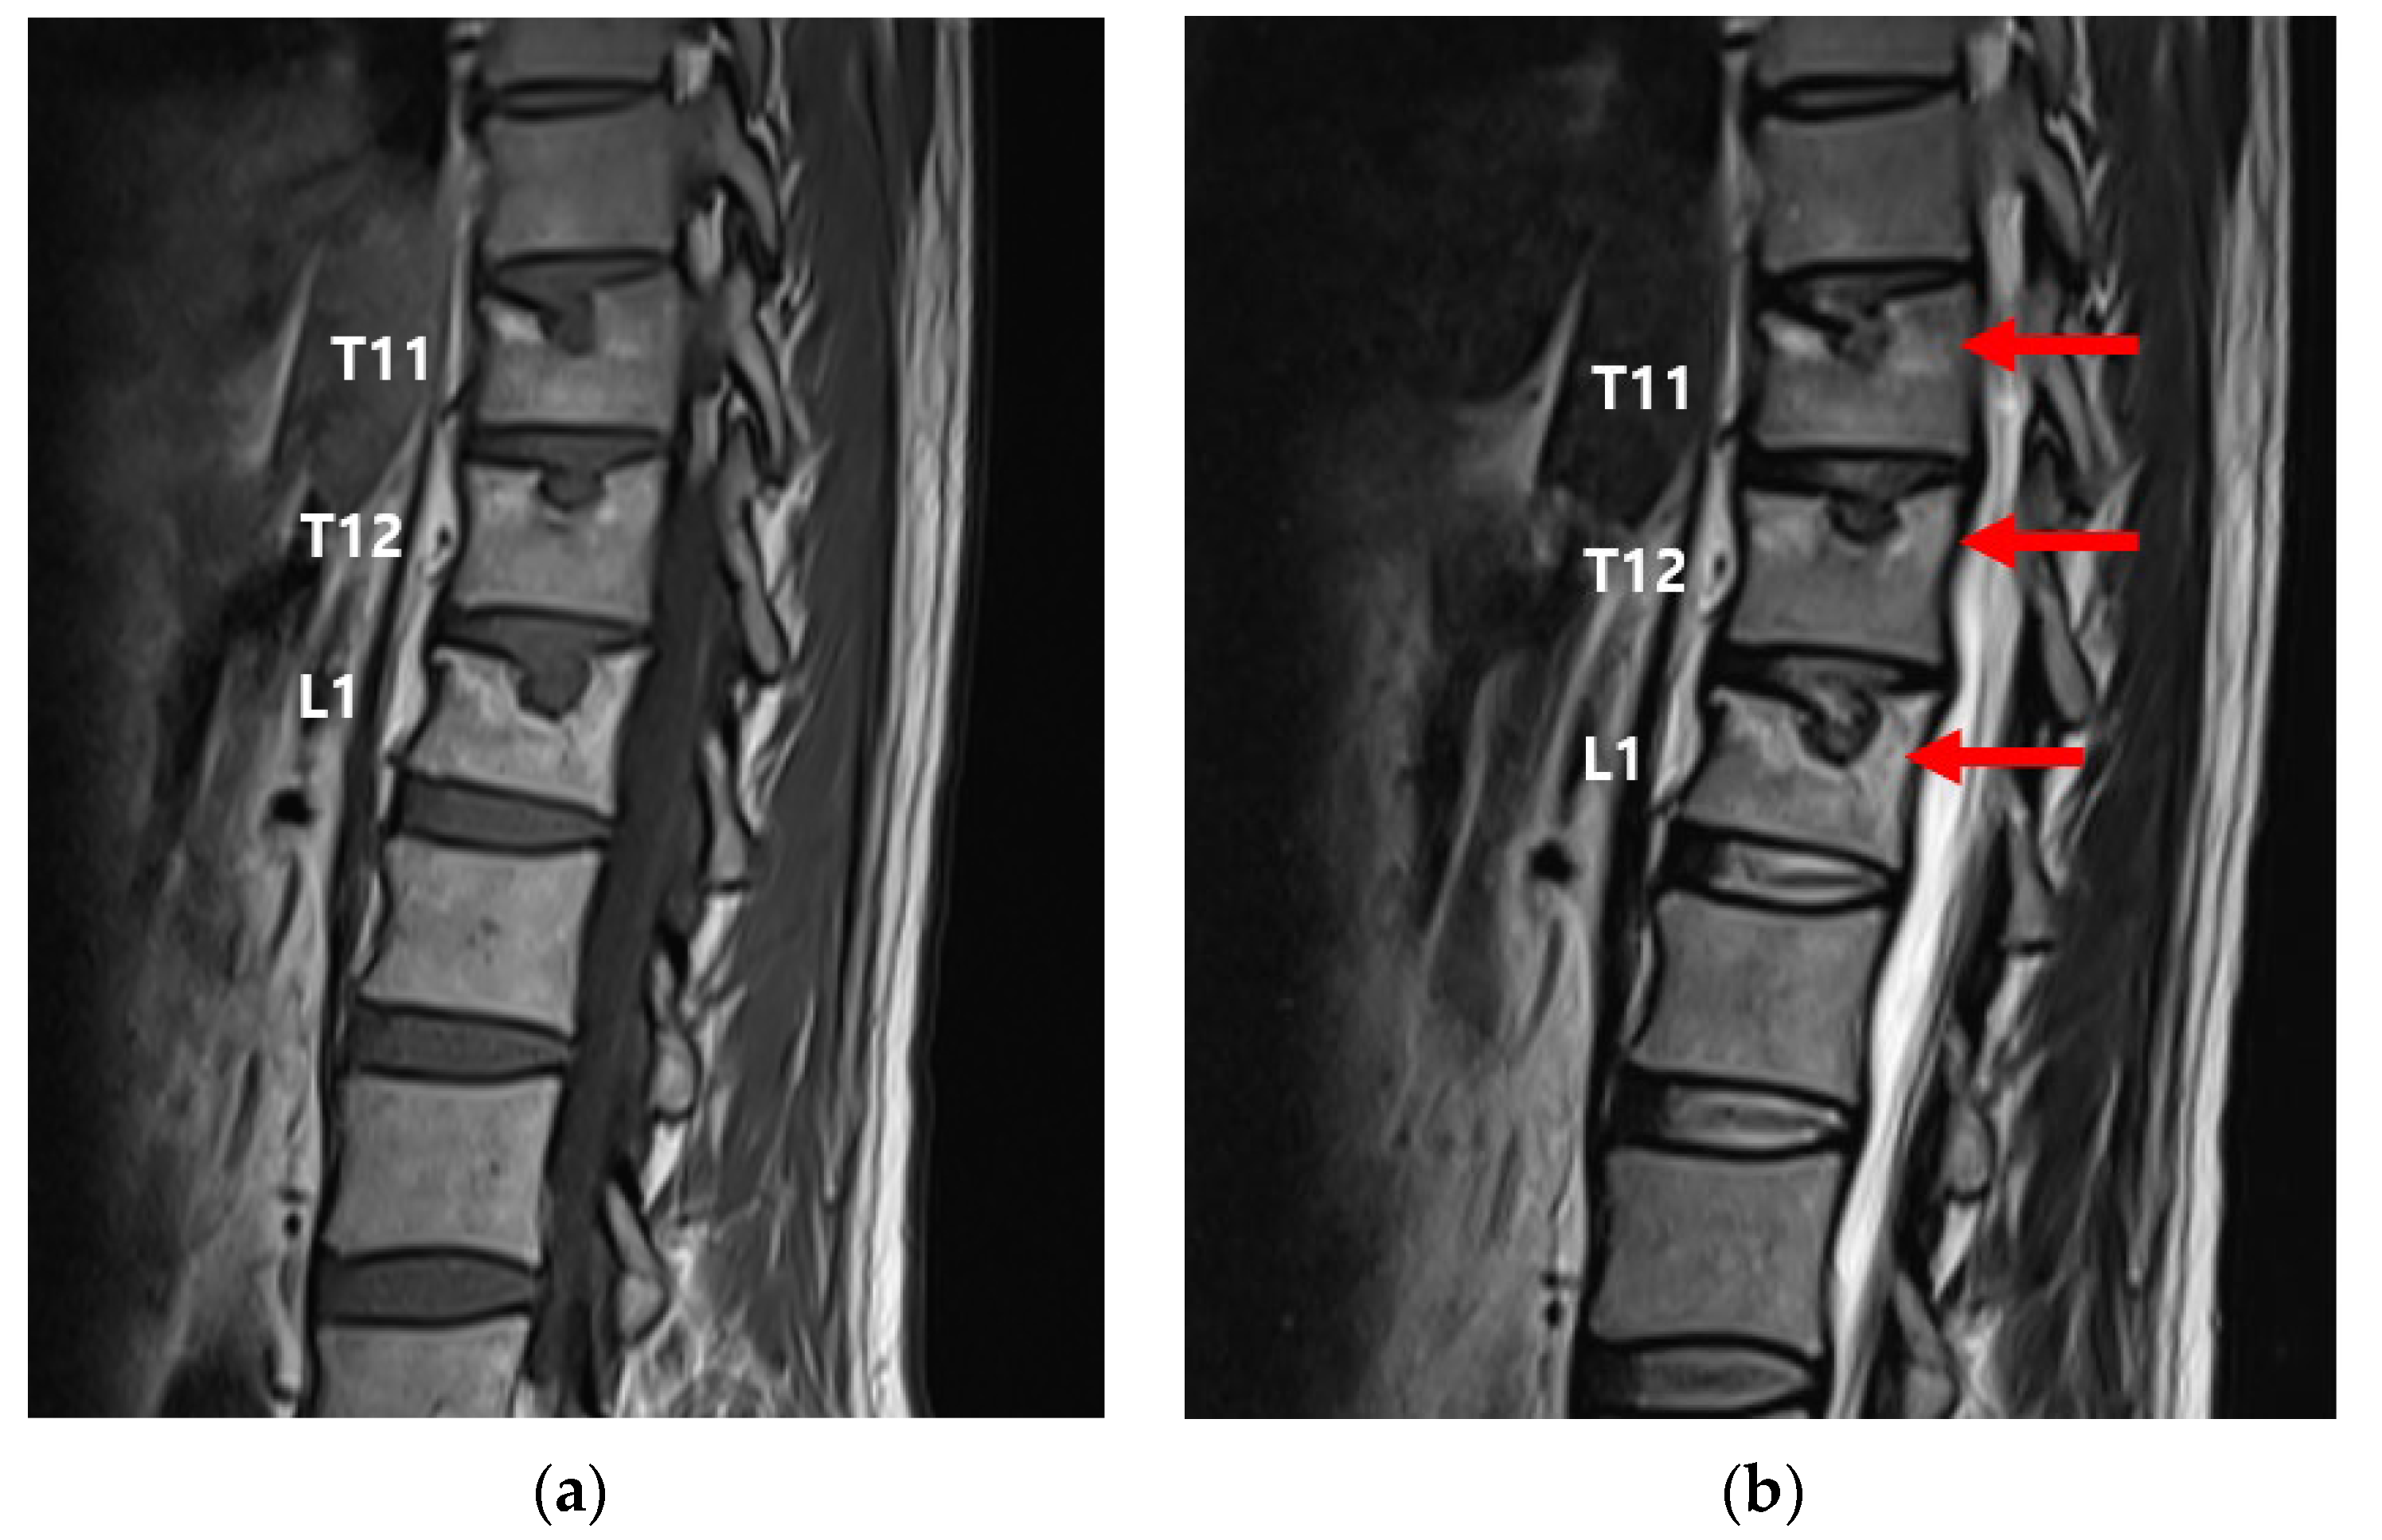

2. Case Presentation